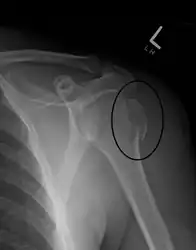

Fracture of the greater tuberosity of the humerus

Multi-fragmented, or comminuted fracture of the proximal humerus with involvement of the greater tuberosity